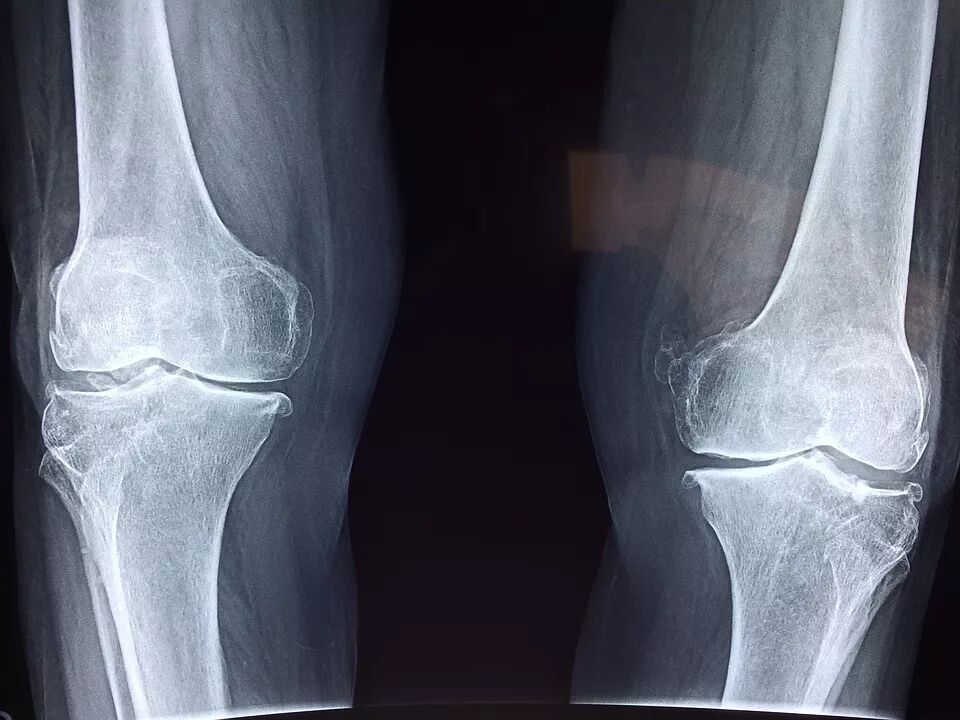

骨关节疾病与心血管疾病及癌症列为威胁人类健康的“三大杀手”,并将每年的10月12日定为“世界骨关节疾病日”。

据世界卫生组织统计,目前全世界有3.6亿人饱受骨关节疾病折磨,而我国骨关节疾病患者总数已超过1.5亿人,60岁以上的老年人有骨关节疾患的占50%以上,70岁以上骨关节发病率达80%。

骨关节疾病一旦患上,患者不但每天忍受疼痛、肿胀的折磨,寝食难安,身心备受摧残,而且一半以上的骨关节疾病患者关节会出现不同程度的强直、畸形,导致关节活动能力丧失,甚至瘫痪,生活不能自理,因此骨关节疾病又被称为称为“不死的癌症”。

健康的软骨,为骨骼提供保护垫,软骨营养成分急剧流失、退化、磨损,会使关节直接摩擦,导致炎症发作!关节肿胀,疼痛,变形,关节疾病,对正常的生命活动,造成严重障碍,各种骨关节疾病,摧残我们的身体,带来无尽痛楚!

肽可以促进骨、软骨细胞增殖,促进组织对钙的吸收;肽可以促进伤口愈合,刺激软骨细胞和成骨细胞的增殖;肽可以改善骨密度,增加骨骺端胶原蛋白的含量,影响破骨细胞的分化和活性,有利于保持松质骨的骨小梁微观结构。

肽可以增加骨骼的强度与硬度,预防骨质疏松和关节炎。

活性肽对骨关节患者,尤其是骨质疏松的患者,具有双向调节作用:一是促进骨细胞的生成数量,改善中老年人的成骨细胞和破骨细胞的相对失衡状态;二是能增加成骨细胞的活性,改善骨细胞的质量,促进与钙的结合,加强骨的钙化和骨的形成。